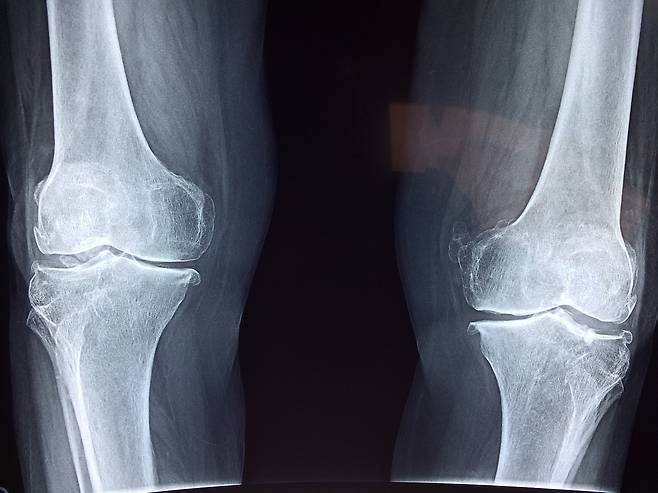

채식하면 고관절 골절 위험이 높아질 수 있다는 연구 결과가 나왔습니다.

고관절 골절은 허벅지 뼈 (대퇴골)의 위쪽 끝(골두)이나

목 부분 (경부)에서 발생하는 골절로

주로 노인들의 낙상이 원인이며 회복이 매우 어렵습니다.